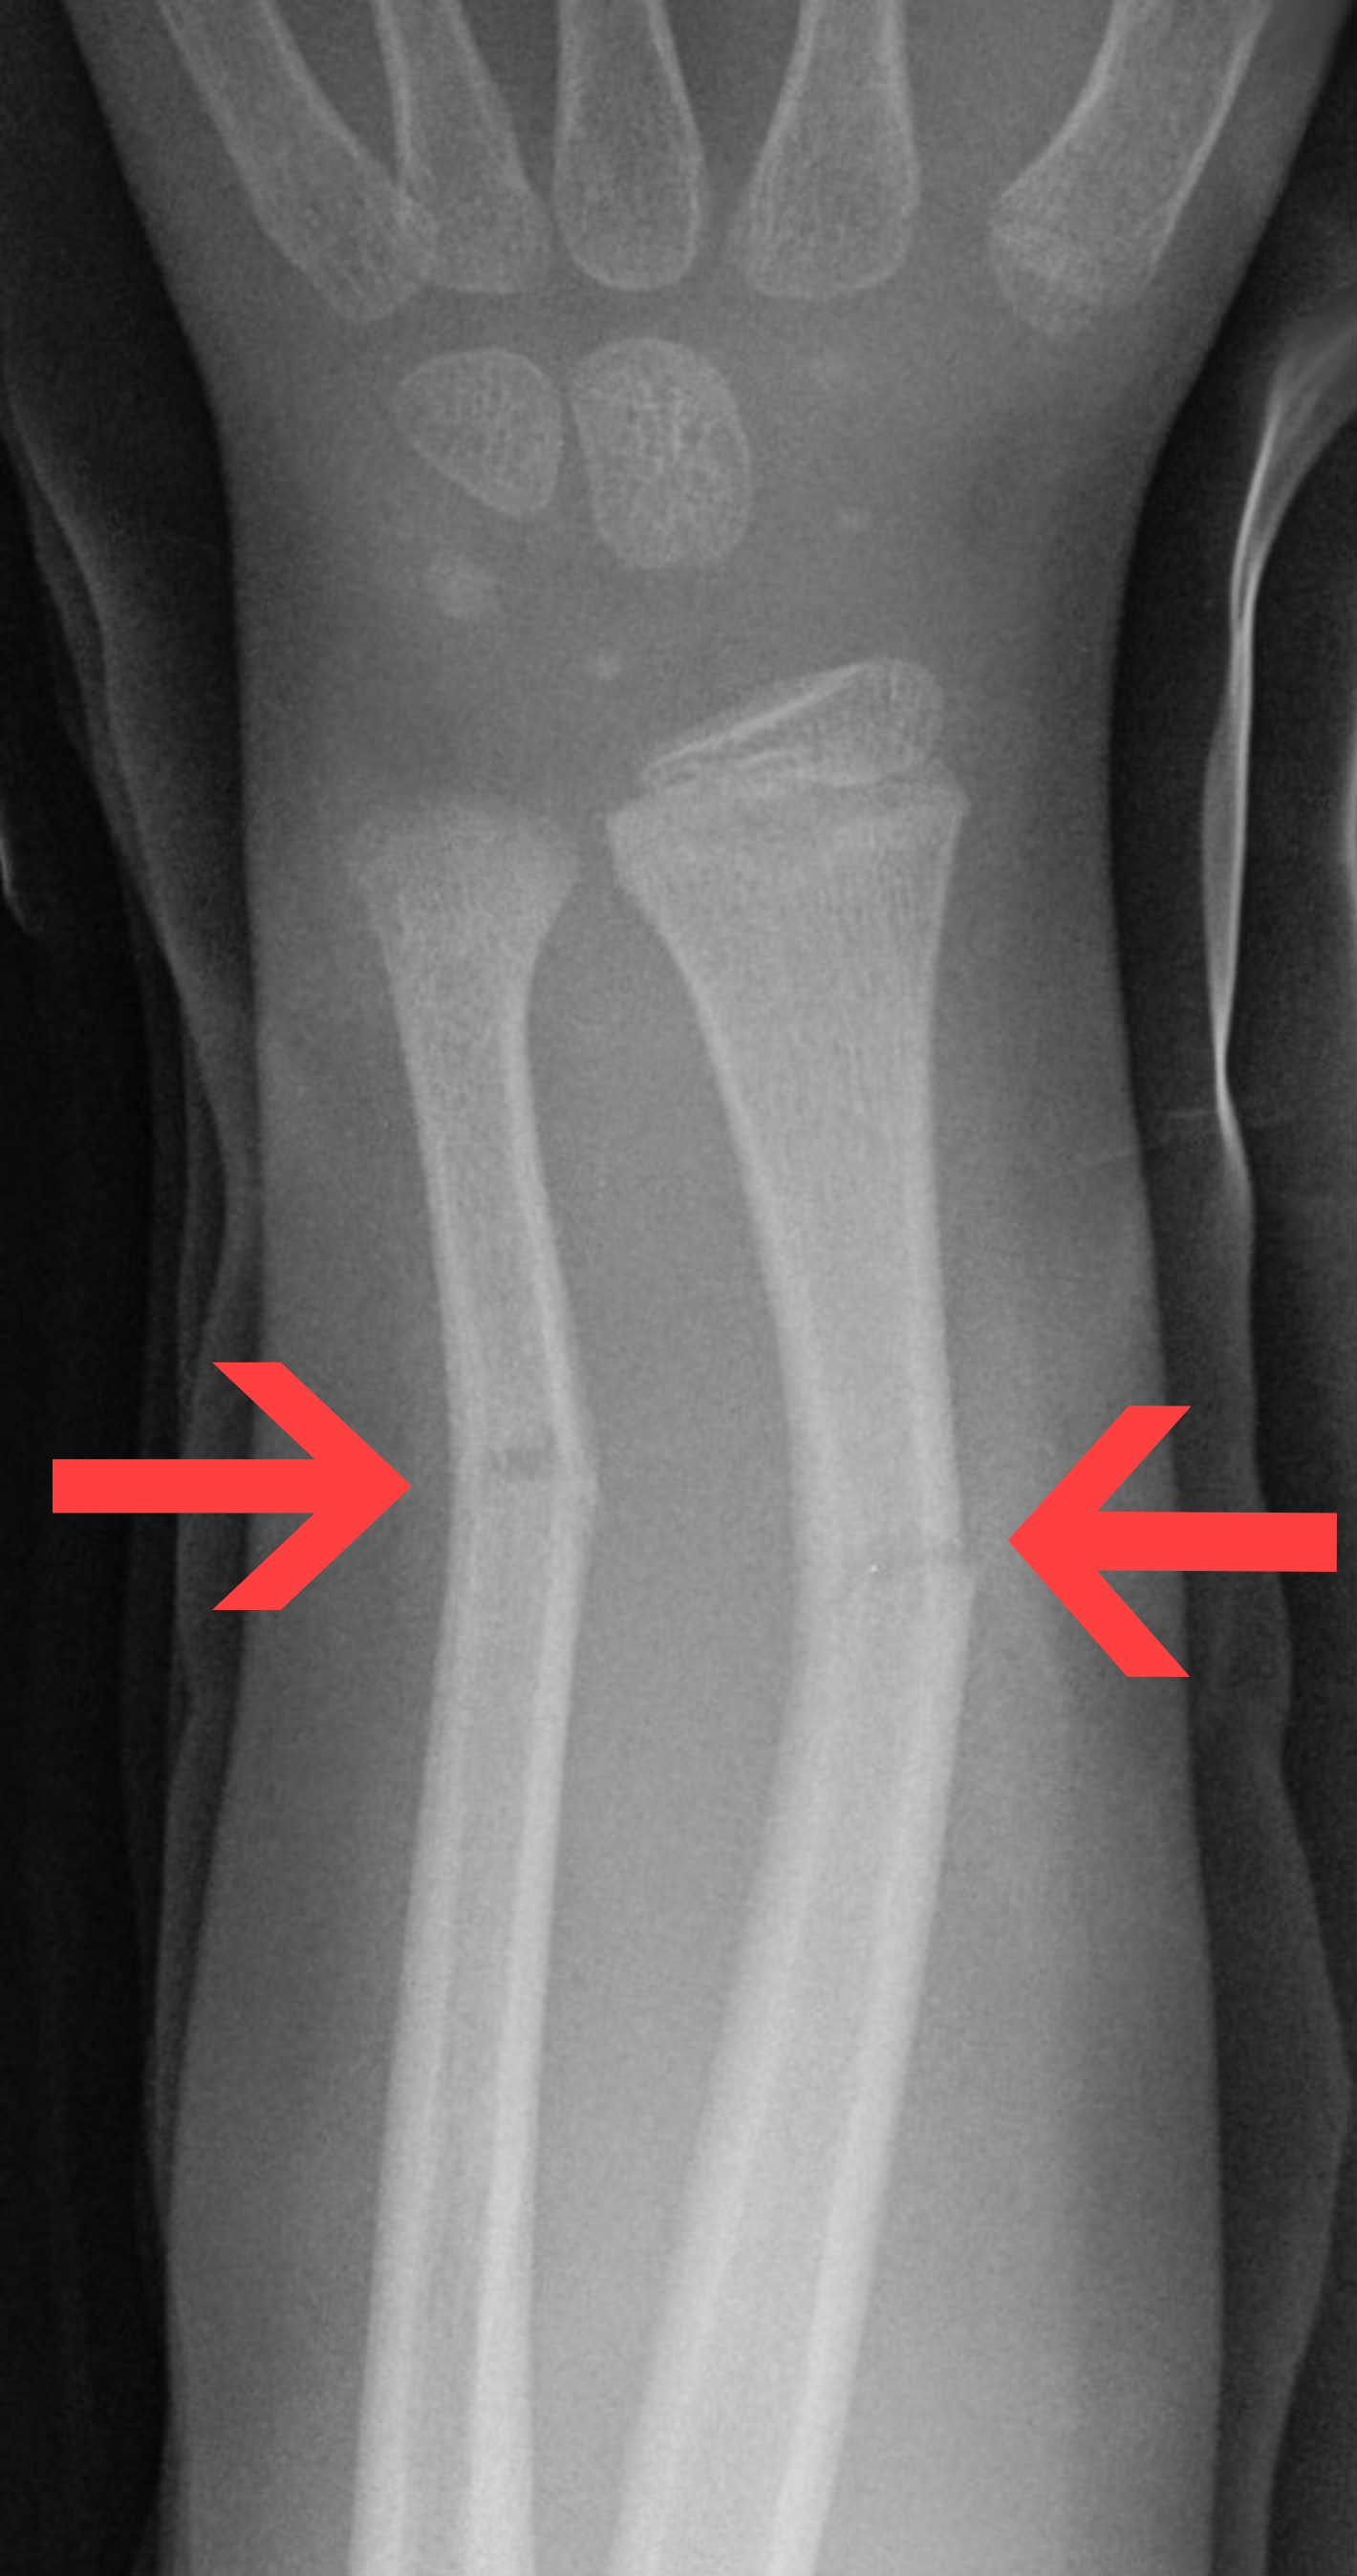

fracture

a break in a bone

types of fractures

open (compound) fracture, closed (simple) fracture, comminuted fracture, greenstick fracture, impacted fracture, and stress fracture

stress fracture

microscopic fissures in bone but no visible break due to repeated, strenuous activities such as running, jumping , or aerobic activities